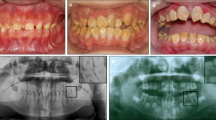

Tooth agenesis can be definitively diagnosed via imaging; however, the treatment options cannot be generalised because tooth agenesis is often associated with alterations and deformities in the tooth structure, delayed eruption and tooth displacement. For instance, patients with tooth agenesis caused by Wnt10B mutation may also have microdontia and taurodontism.75 In patients with tooth agenesis caused by Pax9 mutations, the middle incisors in the upper jaw are susceptible to microdontia,76 and regional odontodysplasia may also occur.77 In addition, tooth agenesis may affect the oral arch length, jaw position and craniofacial morphological features.78,79 Therefore, imaging is necessary for early diagnosis, prompt intervention80 and multidisciplinary treatment to maintain the aesthetic and functional features of teeth.